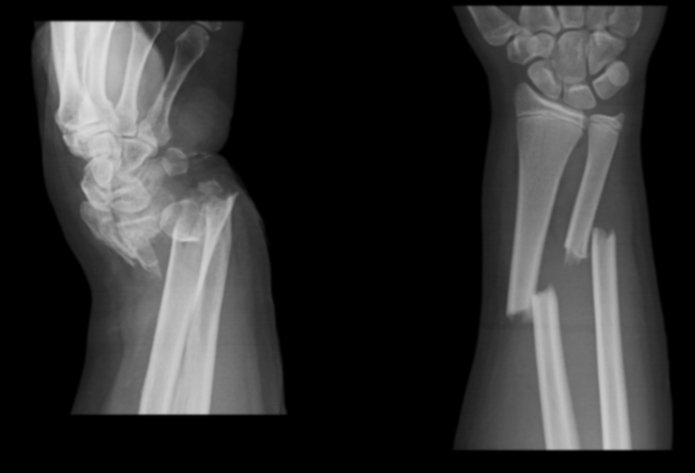

FRACTURES SURGERY

Surgeon for all kind of simple and complex fractures of bones and dislocation of joints.